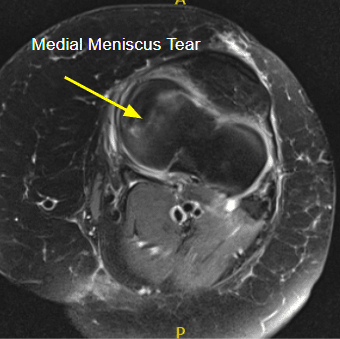

MRI of the left knee suggested radial tear of the medial meniscus and medial collateral ligament sprain/tear.